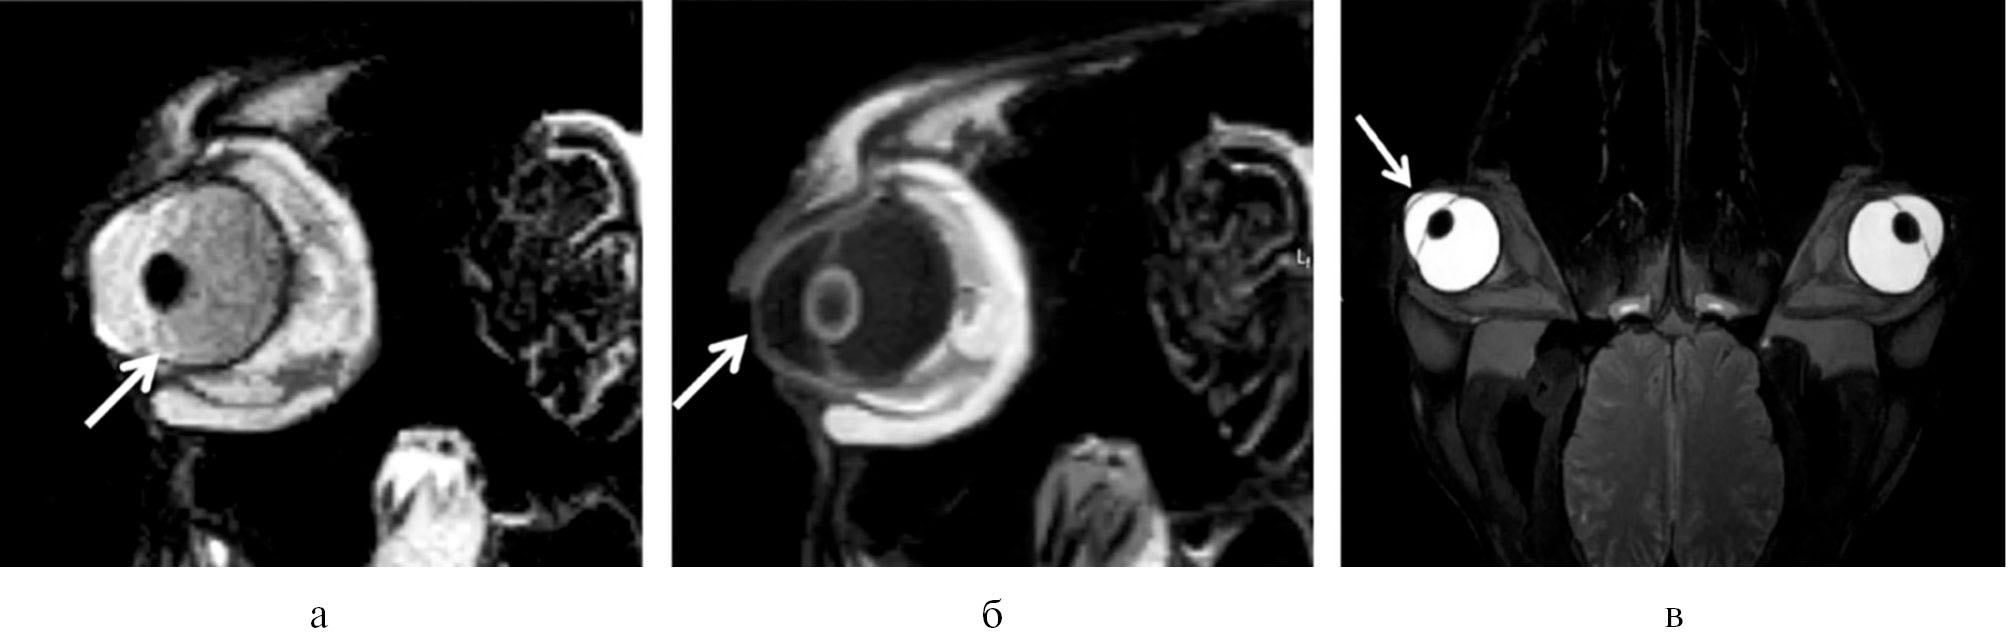

При магнитно-резонансной томографии глазных яблок реснитчатое тело часто имеет аномальный, слегка гиперинтенсивный сигнал с увеличенным и изо- или гипоинтенсивным видом в центре (рис. 2а).

Рис. 2. Магнитно-резонансная томография сканером 0,2 Tesla skanner, Airis Mate с толщиной среза 4 мм: а – аномальное цилиарное тело; б – утолщеная поверхность роговицы; в – гиперинтенсивный карман на утолщенной роговице.

Поверхность роговицы уплотнена (рис. 2б), с гиперинтенсивными карманами (рис. 2в). Периокулярные структуры, включая зрительные нервы, выглядят нормально.